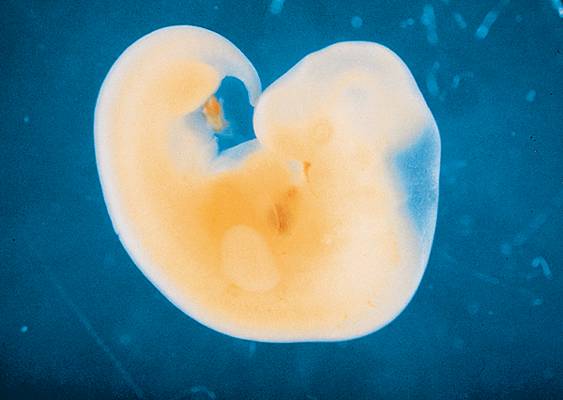

Развитие эмбриона: Что происходит на 3 неделе беременности

Раздел: Фотопанорама